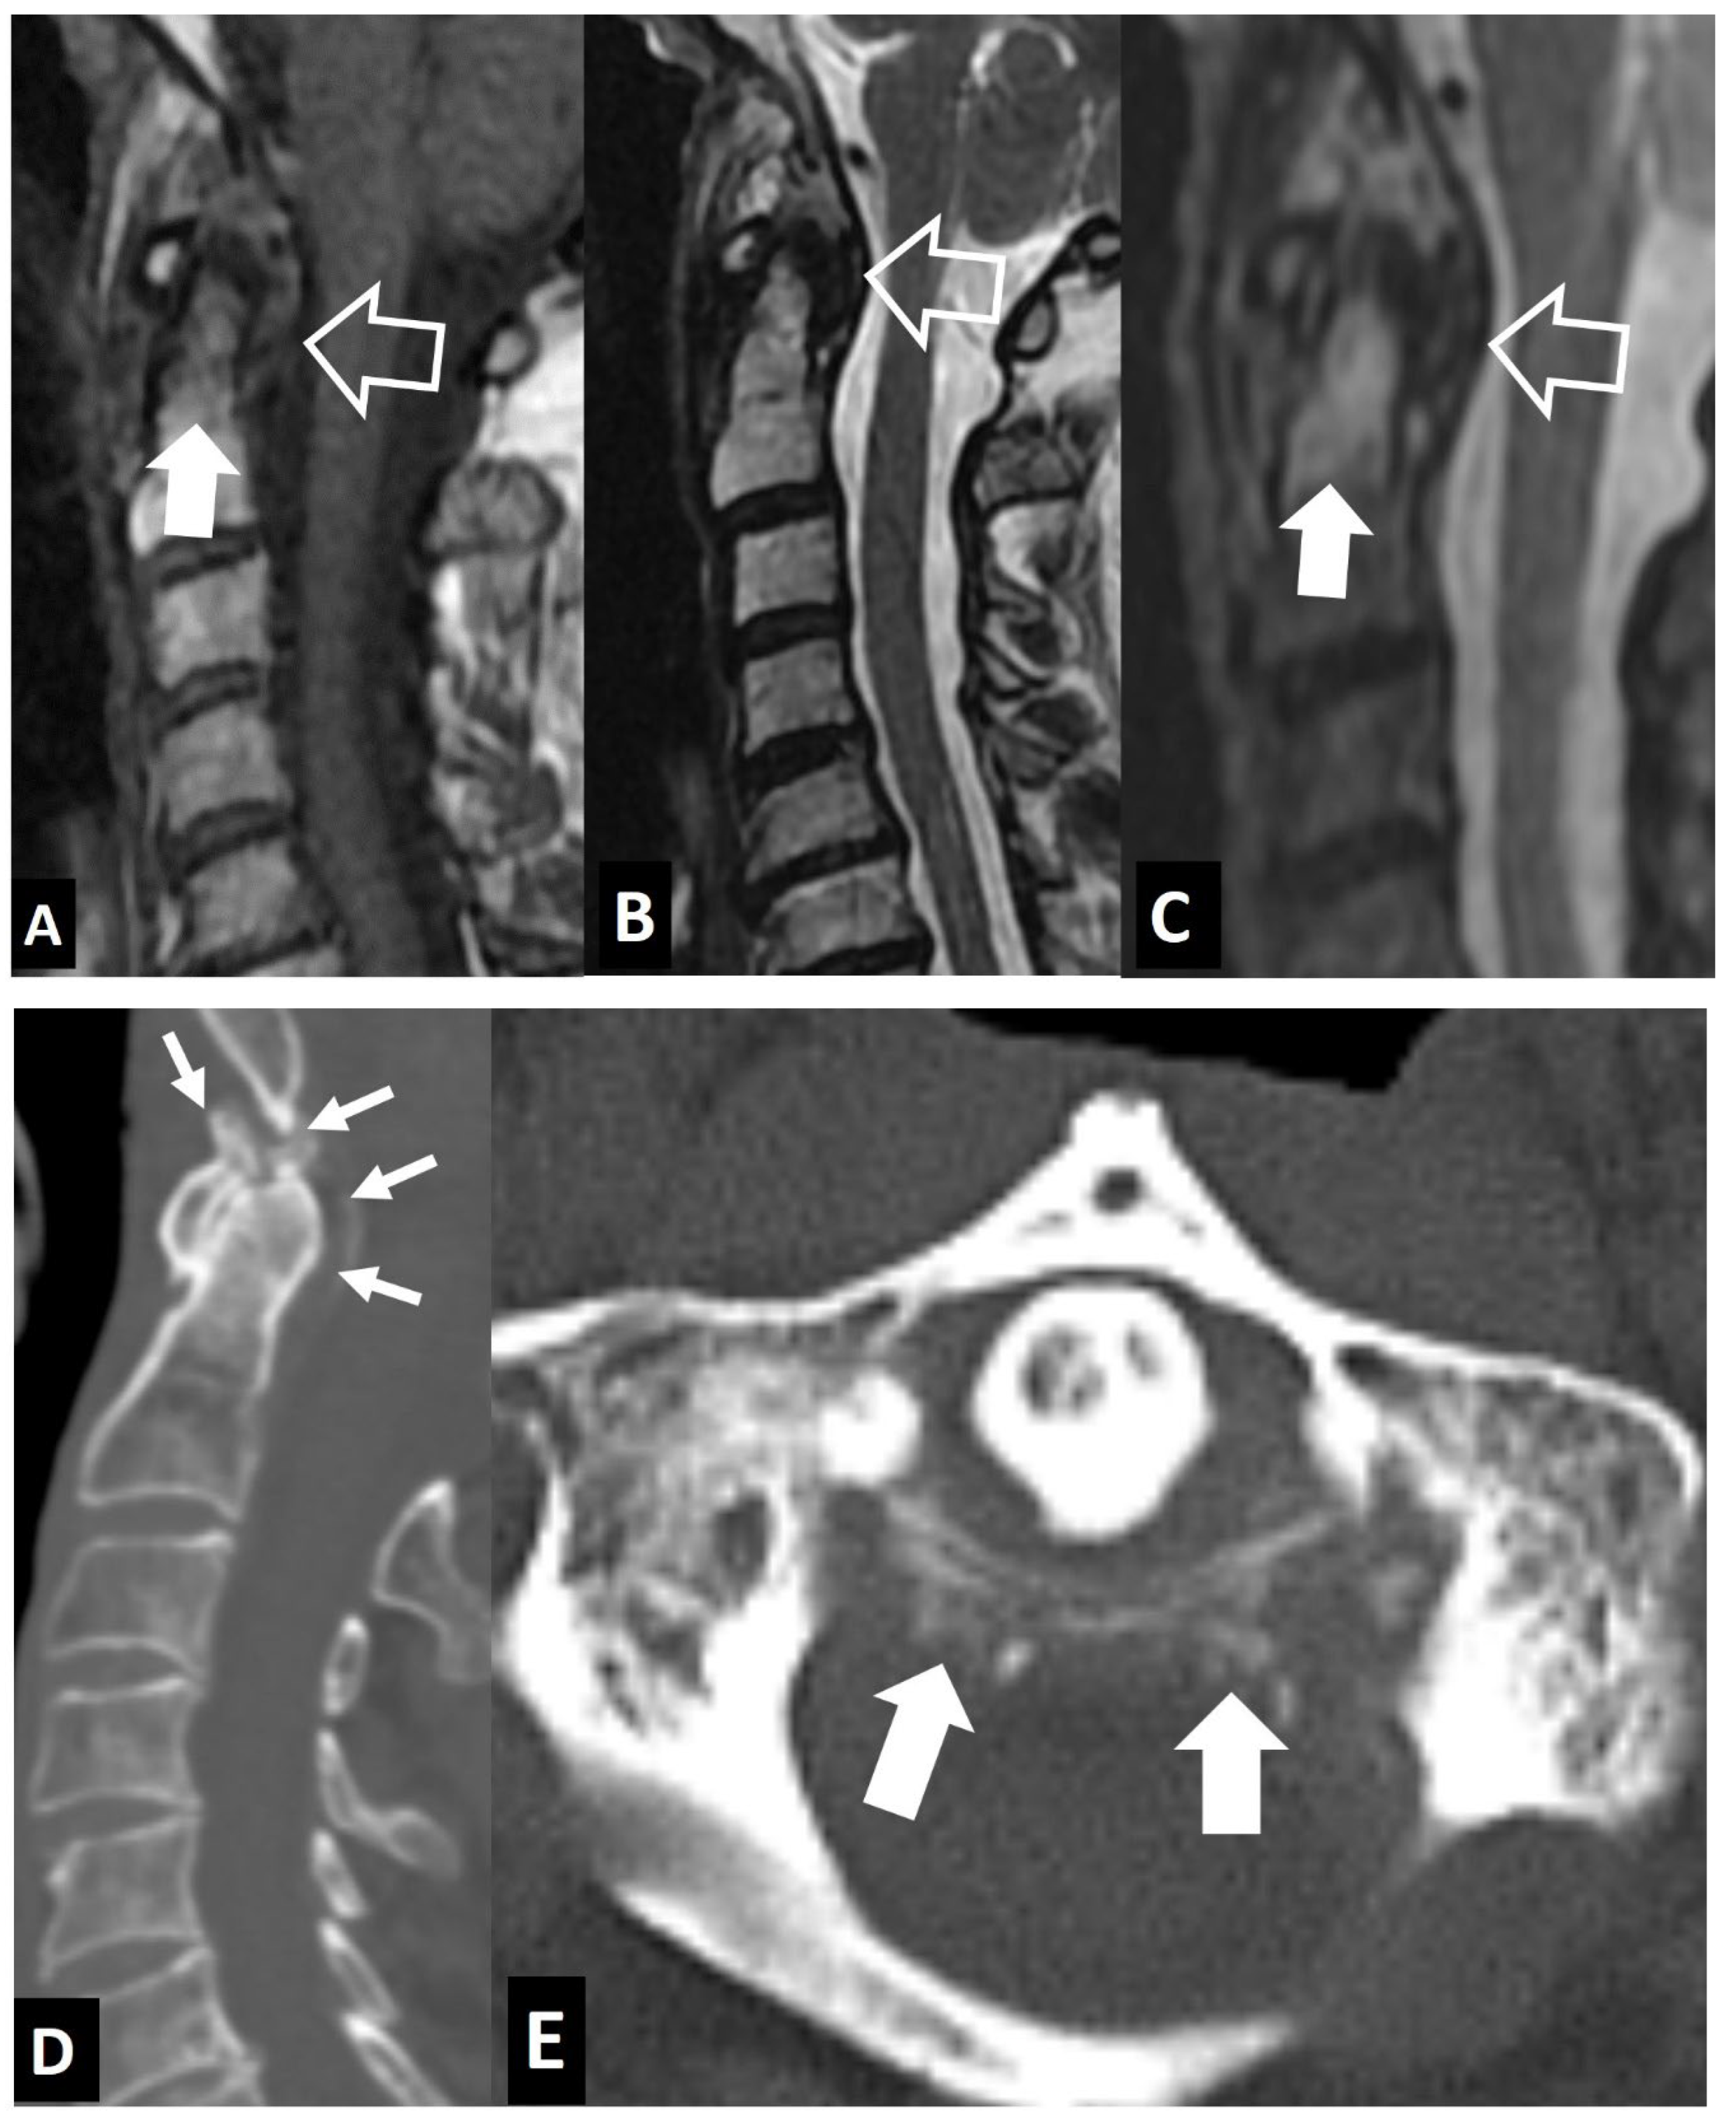

1. b. Non Infectious Sacroiliitis

2. Long Bones